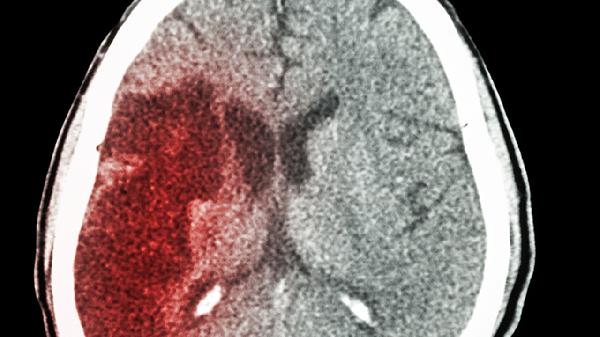

恢复期需定期进行头颅CT或MRI检查,评估出血吸收情况。首次复查通常在出院后1个月进行,之后根据病情每3-6个月复查一次。同时需监测肝肾功能、电解质等指标,评估药物不良反应。如出现头晕加重、行走不稳等新发症状,应及时就诊。长期随访有助于及时发现并处理潜在问题。